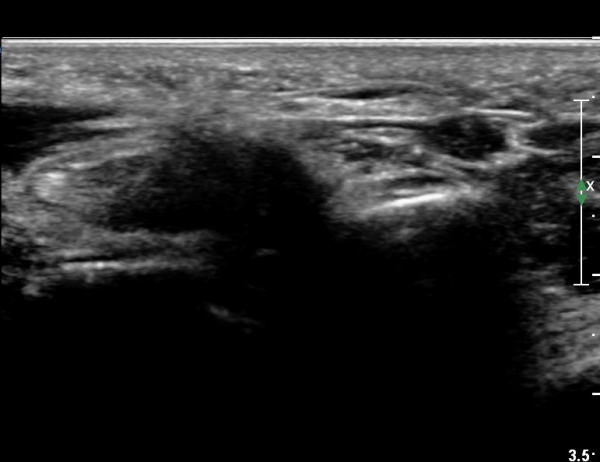

°ËÁö ¿ÜÀü T µî±ÞÀ¸·Î ¾àÈ­µÊ.

¼Õ¹Ù´Ú ºÎÀ§¿¡¼­ ô°ñ½Å°æ ½ÉºÎ °¡Áö º´Áõ

(periphral neuropathy  of  deep palmar branch of ulnar nerve at palm level).